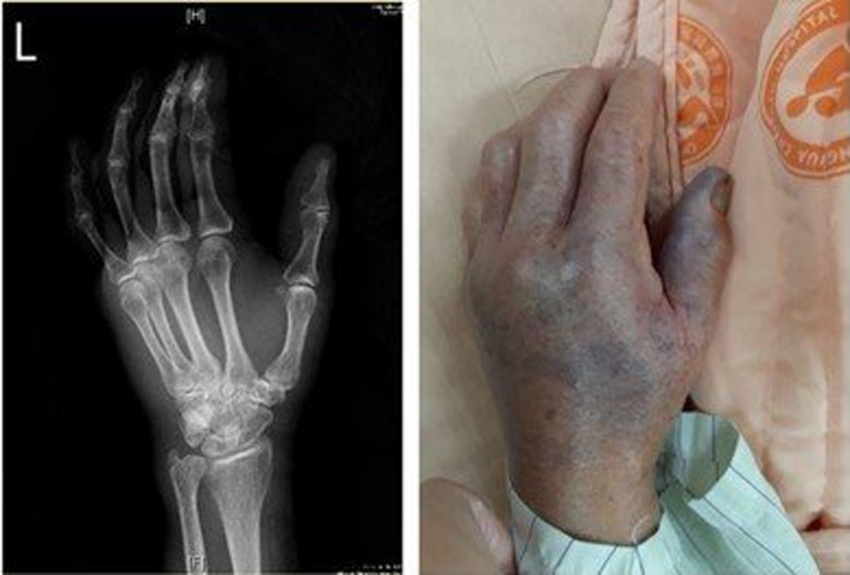

林晏任表示,阿嬤被魚鰭刺傷的傷口不到1公分,刺完馬上就發生紅腫熱痛,而且短短幾小時內手掌就發紫發黑的壞死性筋膜炎。阿嬤送來後快速確診為「創傷弧菌」感染,經快速把紅腫熱痛的患部清創,並給了完整抗生素治療,終於平安出院。

該院急診暨重症醫學部主治醫師林記賢是收治阿嬤的醫師,他表示,當他即時以床邊超音波檢查時就發現阿嬤左手影像上有典型的「鵝卵石狀」積液,立即聯繫整形外科醫師做清創手術,所幸及時清創,因為後來確診為「創傷弧菌」感染,若當時沒有即時清創,阿嬤的手可能嚴重壞死需截肢,還可能併發敗血症等致命風險。